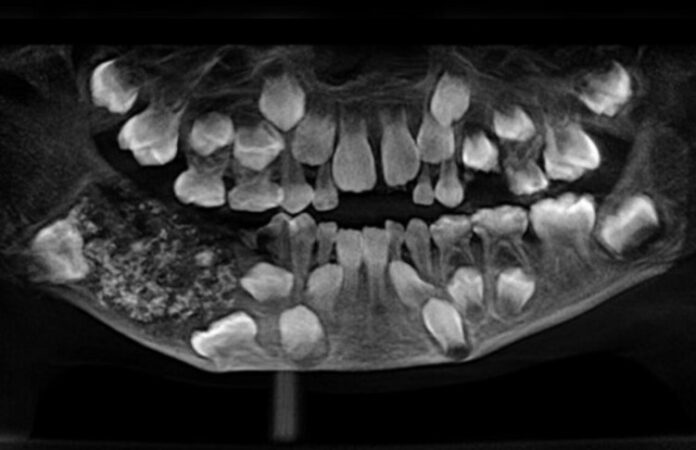

Em 2019, durante uma cirurgia no Saveetha Dental College and Hospital, os médicos encontraram 526 dentes em miniatura dentro de uma massa localizada na mandíbula do garoto.

Os pais notaram o inchaço quando ele tinha apenas 3 anos, mas, devido à pouca idade e à dificuldade de colaboração do menino nos exames, a lesão não foi diagnosticada até crescer de forma evidente. Inicialmente, a família temeu que se tratasse de um câncer na mandíbula, mas a avaliação médica revelou um odontoma composto, tumor benigno formado por tecidos dentários.

A cirurgia retirou uma massa de cerca de 200 gramas, que continha uma espécie de bolsa fechada repleta de pequenas estruturas semelhantes a dentes. O material passou por análise detalhada, confirmando a presença de centenas de “dentículos” agrupados.

Segundo o hospital, foram necessárias cinco horas de trabalho minucioso para remover todos os dentes em miniatura, que lembravam “pérolas dentro de uma ostra”.